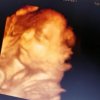

Razvoj bebe

Bebi rastu nokti na nogama i rukama. Uvećava se i količina masnog tkiva ispod kože i dete počinje ubrzano da dobija na težini. Sada već počinje da zauzima pravi položaj “bebe u stomaku” – sa prekrštenim rukama i nogama. Nastavlja se ubrzani rast mozga i povećava se veličina glave jer sve veći mozak oblikuje lobanju. Dužica je obojena a zenica reaguje na svetlo. Kose na glavi je sve više. Težina bebe je oko 1320 gr a dužina oko 40 cm.

Napomena: Svaka beba individualno se razvija u majčinom stomaku.